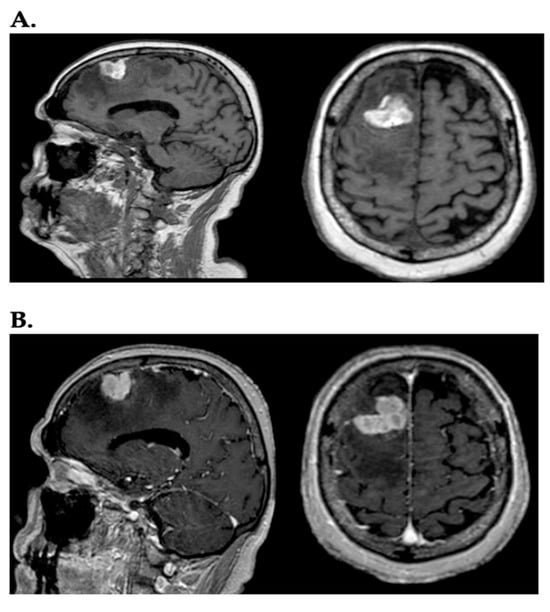

Melanoma is considered the most aggressive skin tumor and accounts for 90% of deaths related to skin cancers []. In a recent study, it was observed that the incidence of melanoma has risen sharply among individuals over 60, and rates are expected to keep increasing for decades to come []. Melanoma is a leading cause of metastases in the central nervous system (CNS), representing 6–12% of all metastatic brain tumors []. Between 40% and 75% of patients with stage IV melanoma develop brain metastases (BMs), highlighting the remarkable capacity of melanoma to colonize the brain []. Melanoma brain metastases (MBMs) are linked to a poor prognosis, directly causing death in 60–70% of melanoma patients. Magnetic resonance (MR) is the gold standard for detecting and assessing malignant brain tumors, including BMs (Figure 1) [].

Figure 1.

(A) In the sagittal and axial planes, a lesion, heterogeneously hyperintense, with irregularly oval morphology and diffuse perilesional edema, is visible in the right frontal region on T1-weighted images; (B) the same lesion after administration of contrast (gadolinium) assumes intense contrast enhancement.